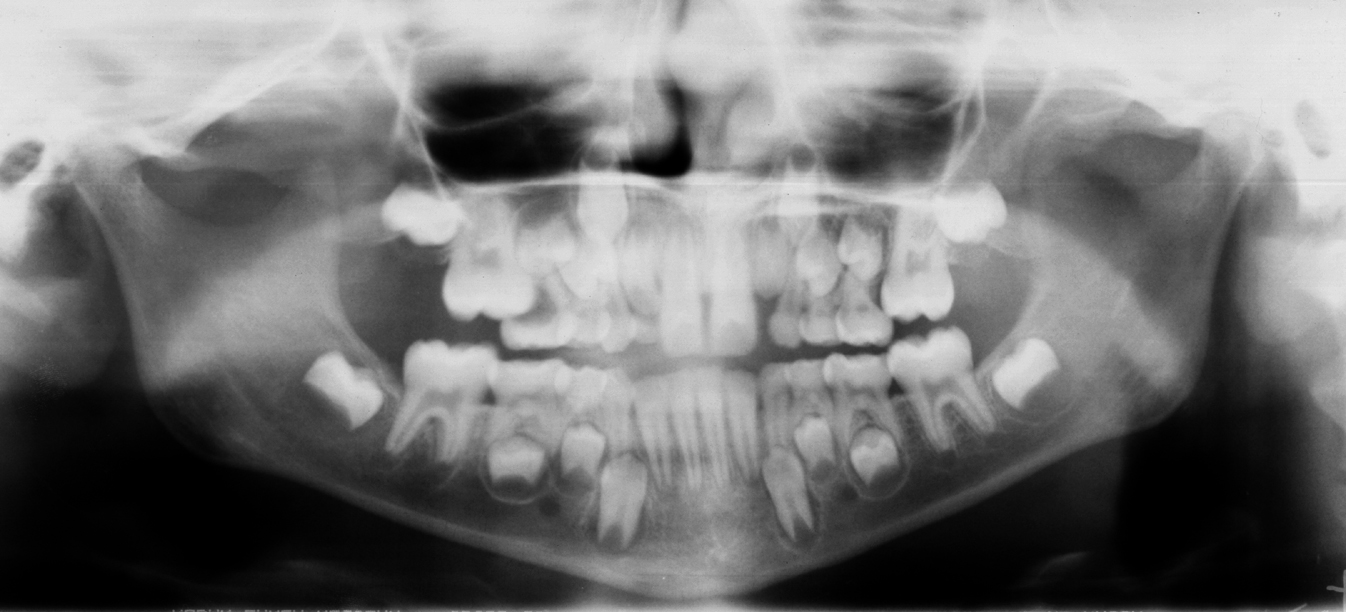

Brass Wire Ectopic Eruption . Ectopic eruption of pmfm is a common eruption disorder occurring during mixed dentition. Ectopic eruption (ee) is defined as a localized disturbance in the eruption path of a tooth leading to an abnormal position or orientation of that tooth. Ectopic eruption of permanent molars is one of the challenges that arise in the early mixed dentition period, particularly when the root of the primary. Ee of permanent first molars is observed when the molar assumes an abnormal mesioangular path of eruption, resulting in an impaction at the distal aspect of the primary second molar. If left untreated, many problems could arise, such. Ectopic eruption of a first permanent molar reflects an abnormal mesioangular path, leading to resorption of the adjacent second primary molar and potential loss of space for the eruption of the second permanent bicuspid. Sert the distorted brass wire can cause soft tissue damage.

Ectopic eruption of permanent molars is one of the challenges that arise in the early mixed dentition period, particularly when the root of the primary. If left untreated, many problems could arise, such. Ectopic eruption of a first permanent molar reflects an abnormal mesioangular path, leading to resorption of the adjacent second primary molar and potential loss of space for the eruption of the second permanent bicuspid. Ectopic eruption of pmfm is a common eruption disorder occurring during mixed dentition. Ee of permanent first molars is observed when the molar assumes an abnormal mesioangular path of eruption, resulting in an impaction at the distal aspect of the primary second molar. Sert the distorted brass wire can cause soft tissue damage. Ectopic eruption (ee) is defined as a localized disturbance in the eruption path of a tooth leading to an abnormal position or orientation of that tooth.

Brass Wire Ectopic Eruption If left untreated, many problems could arise, such. Ectopic eruption of permanent molars is one of the challenges that arise in the early mixed dentition period, particularly when the root of the primary. Ectopic eruption of a first permanent molar reflects an abnormal mesioangular path, leading to resorption of the adjacent second primary molar and potential loss of space for the eruption of the second permanent bicuspid. Ectopic eruption of pmfm is a common eruption disorder occurring during mixed dentition. Ee of permanent first molars is observed when the molar assumes an abnormal mesioangular path of eruption, resulting in an impaction at the distal aspect of the primary second molar. Sert the distorted brass wire can cause soft tissue damage. Ectopic eruption (ee) is defined as a localized disturbance in the eruption path of a tooth leading to an abnormal position or orientation of that tooth. If left untreated, many problems could arise, such.